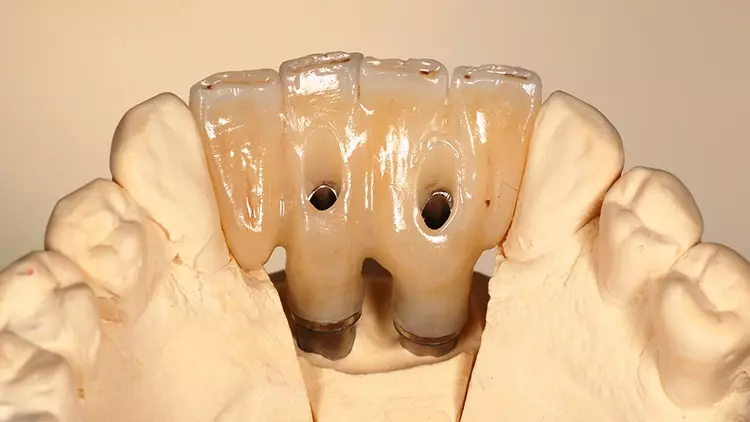

Der vorliegende Patientenfall beschreibt die Implantatversorgung im Ober- und Unterkiefer-Frontzahnbereich eines älteren Patienten mit einer chronischen Parodontitis und ohne systemische Erkrankungen bzw. ohne eine regelmäßige Einnahme von Medikamenten. Infolge des Attachmentverlusts konnte trotz einer Ridge Preservation mittels Sofortimplantation und einer bukkalen Auflagerung von xenogenem Knochenersatzmaterial insbesondere im Bereich der Interdentalpapillen des Oberkiefers kein ausreichender Weichgewebserhalt in vertikaler Richtung erzielt werden, was auf den Attachmentverlust infolge der Parodontitis zurückgeführt werden kann. Daher war es notwendig, die fehlenden Papillen mittels rosa eingefärbten Zirkonoxids in die Restauration zu integrieren (Abb. 13 und 14).

Der Patient wurde entsprechend instruiert, diese Bereiche täglich mittels Interdentalbürsten zu reinigen. Rezessionen wurden nicht beobachtet, was auf den dicken Phänotyp des Patienten zurückgeführt werden könnte [5]. Trotz der geringen Einschränkungen im Bereich der rot-weißen Ästhetik war der Patient mit dem ästhetischen Gesamtergebnis zufrieden.